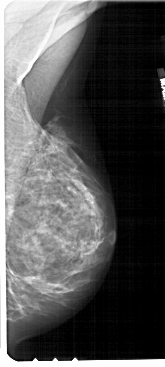

A_1724_1.LEFT_CC

LEFT_CC LINES 5491 PIXELS_PER_LINE 2806 BITS_PER_PIXEL 12 RESOLUTION 43.5 OVERLAY